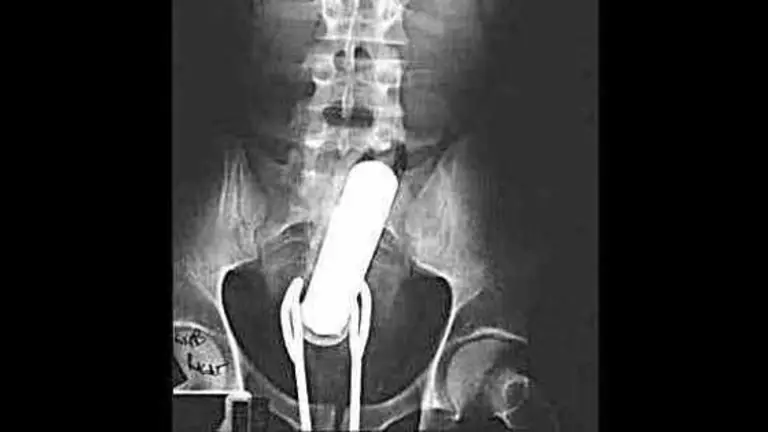

Los médicos interrogaron al paciente y luego le realizaron una radiografía que reveló que el hombre tenía un frasco en el recto, añadió.